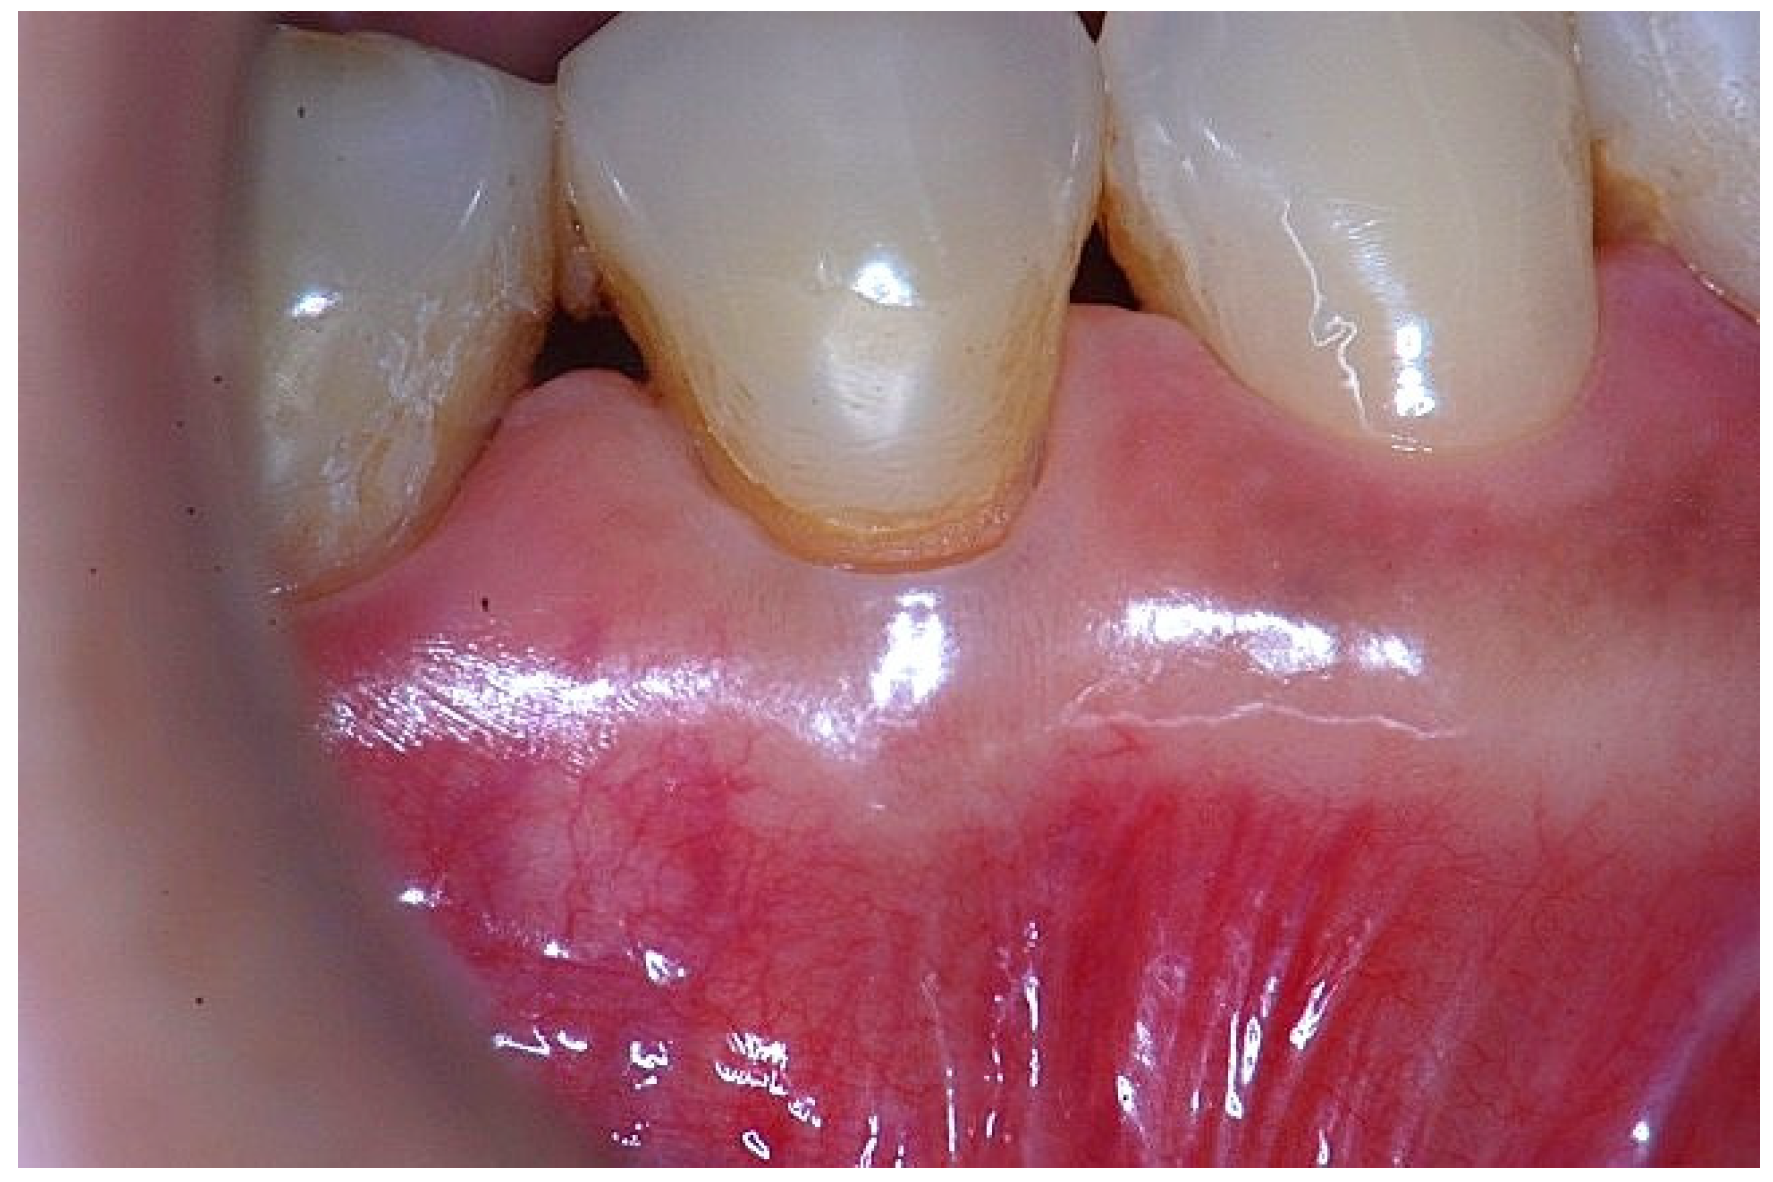

Figure 3. Apical displacement of the gingival margin observed during deep lip retraction.

In a clinical scenario characterized by 2 mm of keratinized tissue and a sulcus depth of 1 mm, a stable and mechanically resistant connective tissue attachment is not present [1]. This is attributable to the fact that most connective tissue fibers inserting into the root surface are associated with non-keratinized, mobile mucosal tissues (Figure 1), which are elastic in nature and therefore incapable of stabilizing the gingival margin (Figure 2 and Figure 3). In contrast, when these fibers are embedded within keratinized tissue, they are firmly anchored to both the tooth and alveolar bone and are comparatively immobile, thereby contributing to gingival margin stability (Figure 4, Figure 5 and Figure 6).